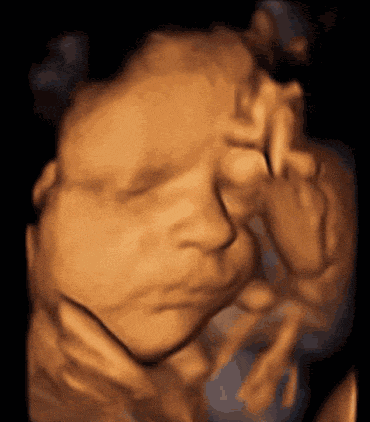

自怀孕后

很多宝妈都一直好奇

自己的宝宝长什么样子

在心中预想了无数次

终于熬到了孕中期

可以借着四维彩超

一睹宝宝的真颜